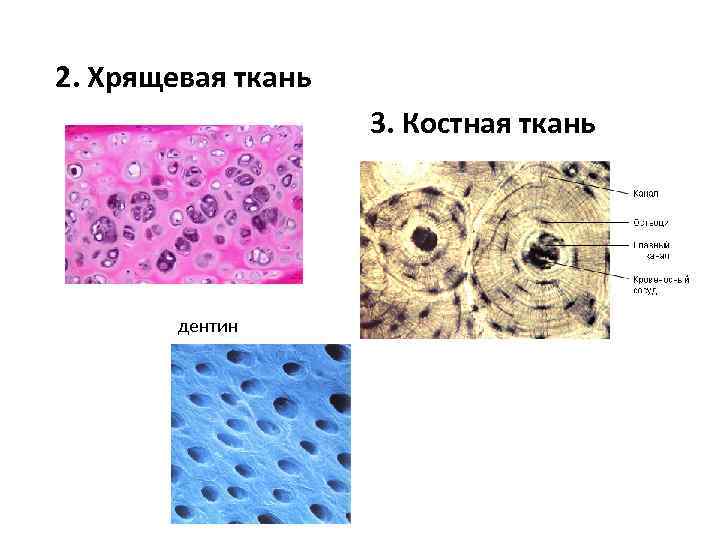

Структура грубоволокнистой костной ткани: наглядные примеры